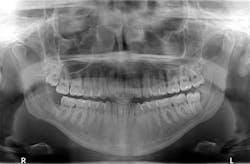

Figure 6: Patient’s three-month radiograph

Bone has filled in, no paresthesia is present, and there are no recurrent lesions or abnormal cell formation. No. 17 will be monitored closely with plans for removal when the bone on the right side has healed sufficiently. Figures 6 and 7 are three-month and six-month radiographs, respectively.

Figure 7: Patient’s six-month radiograph